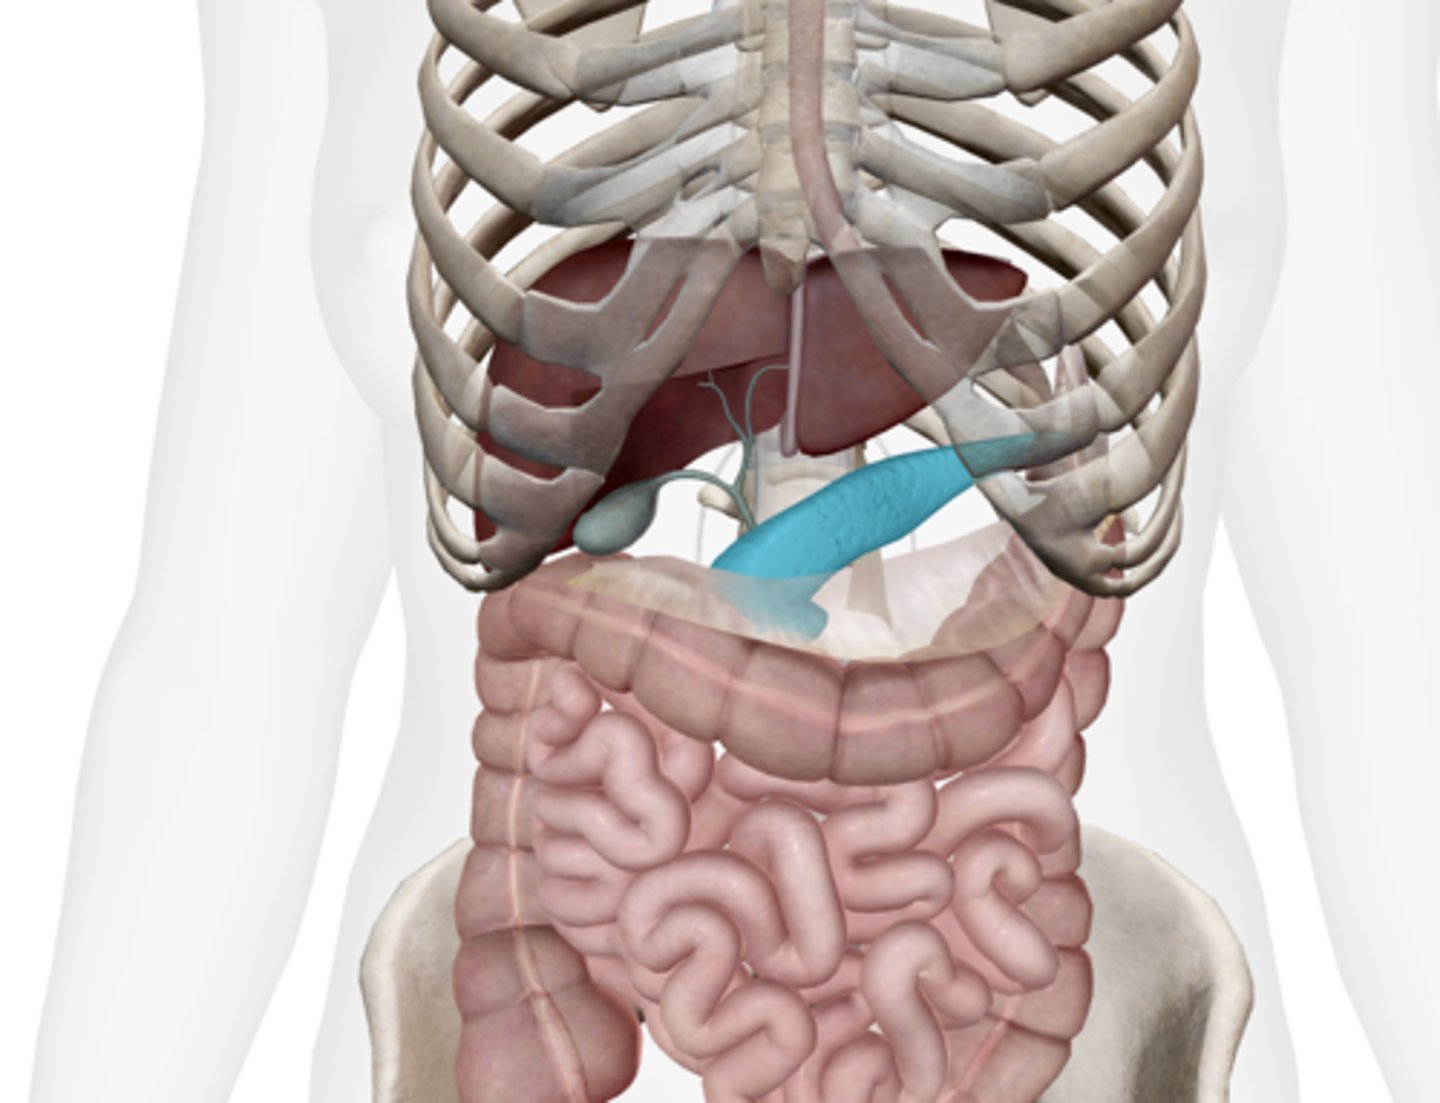

Gallbladder

Cystic duct

Common hepatic duct

Common bile duct

Pancreas

Main pancreatic duct (duct of Wirsung)

Accessory pancreatic duct (duct of Santorini)

Liver

Duodenum